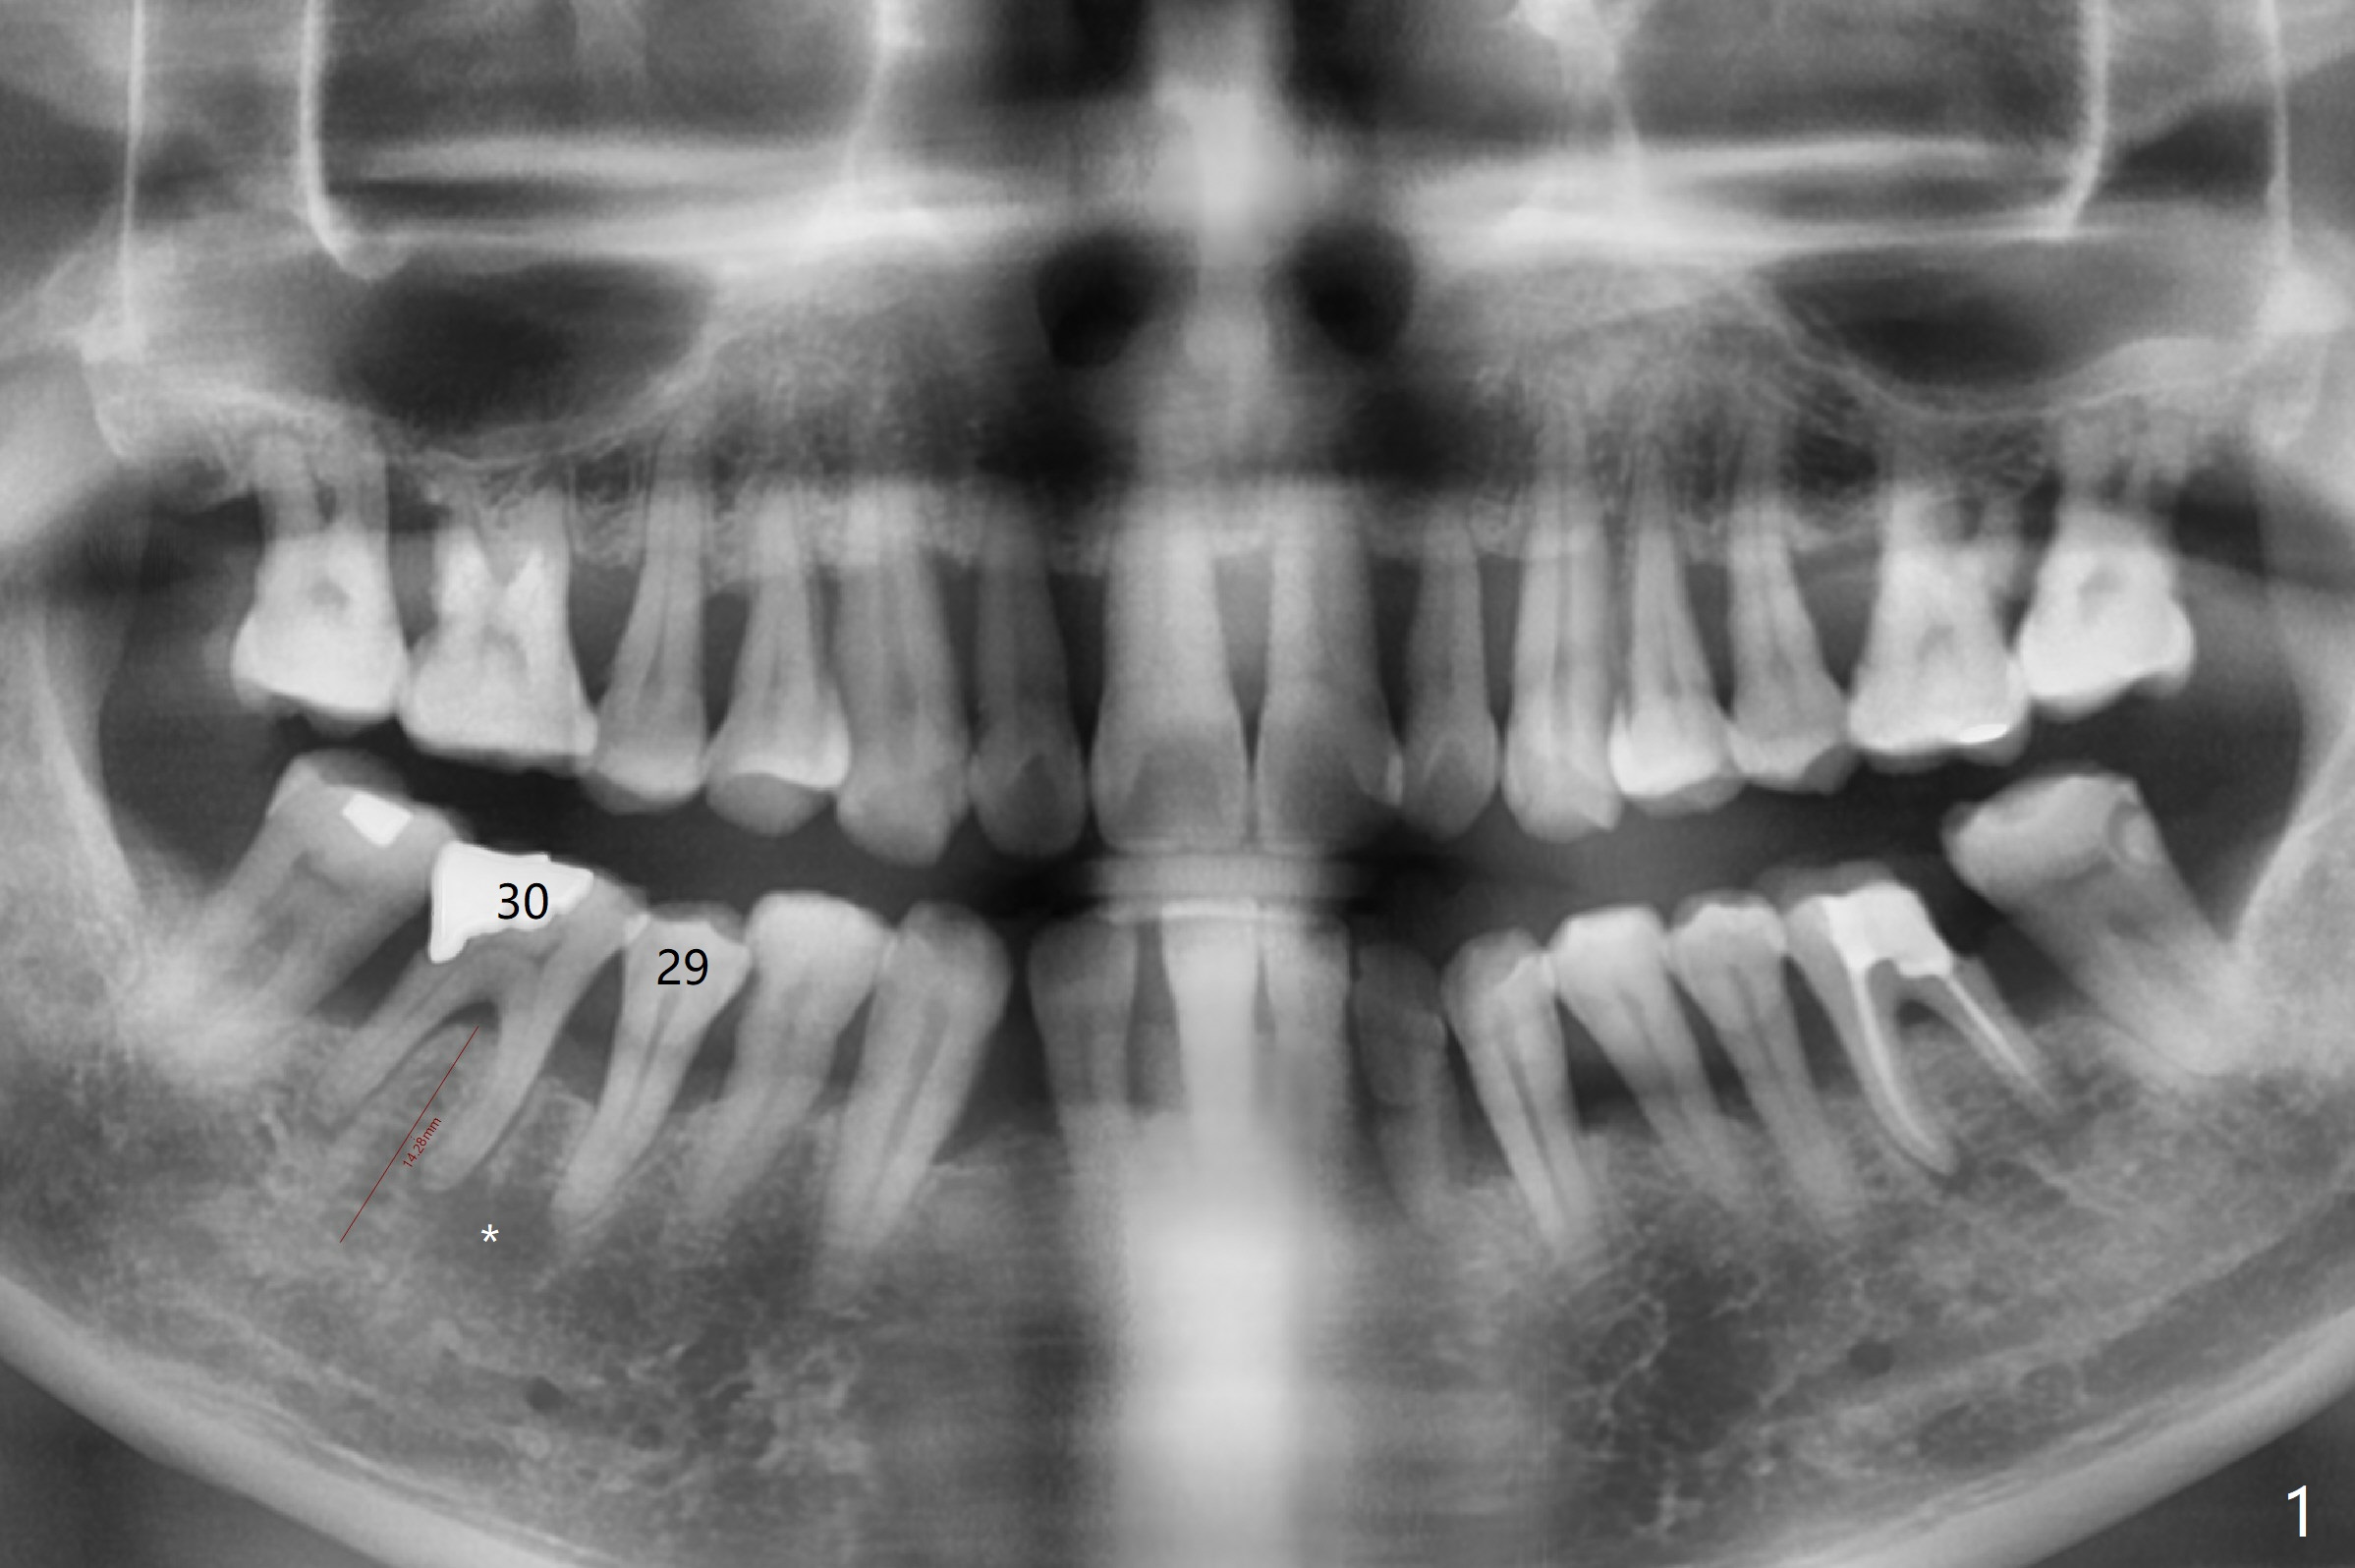

A 60-year-old man (smoker, 1/3 to 1/2 ppd) with large DO amalgam at #30 develops pain and mild swelling apparently apical to #29 (Fig.1-3). Both teeth (having fused PARL (periapical radiolucency) *) have mild percussion with the tooth #29 having higher mobility. CBCT shows apical defect (Fig.3 >). Three weeks earlier, the tooth #19 had much more severe infection with a similar apical defect (Fig.4 >). Combined with history of repeated infection associated with #30, the tooth is extracted with difficulty in obtain sound anesthesia. Socket preservation is performed instead of immediate implant (Fig.5 (*: Vanilla Graft)). CBCT makes it easy to diagnose 2 canals at #28 (Fig.6 as compared to Fig.2). Pain gradually decreases 3 days postop. In fact he has hypertension and smokes.

The bone seems to be wide to hold a 5x11.5 mm implant if it is placed early post extraction (Fig.7). Probably due to smoking, the socket appears to heal slow (Fig.8,9). There is mild palpation pain in the buccal vestibule. The tooth #29 remains mobile. The patient is scheduled to return for follow up in 2 months. A 5x5 cm scan is taken for the lower right posterior area for guided surgery.